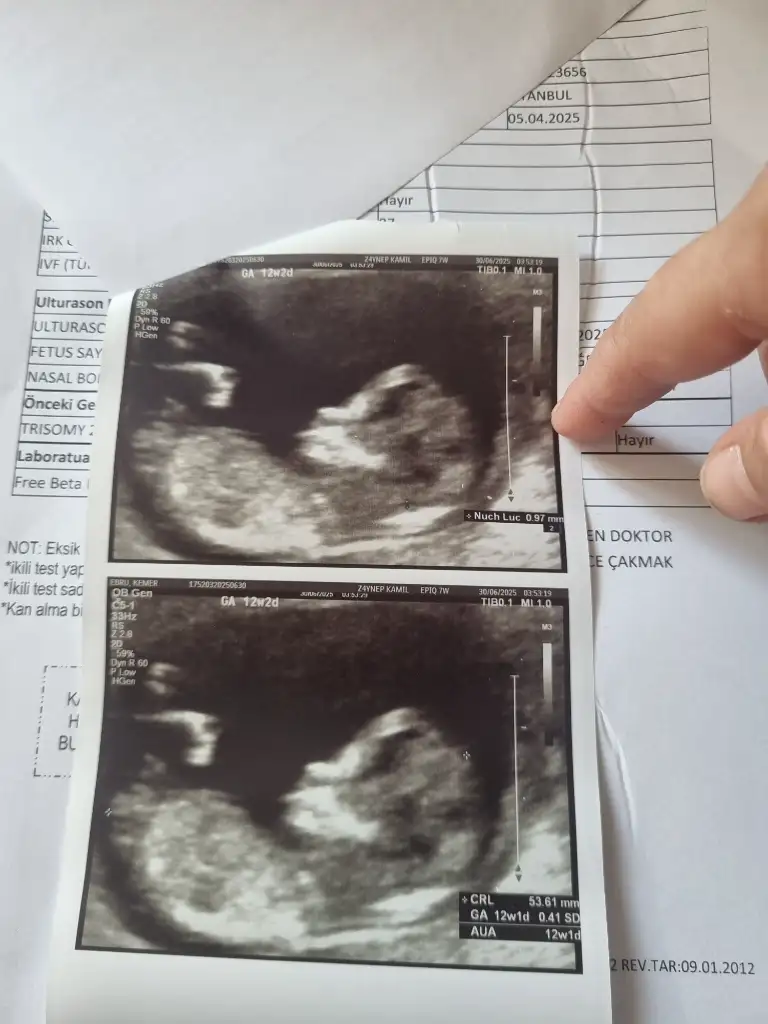

Günaydın canım. Allah bağışlasın. Kız gibi geldi banaBenimde bakarmısınıs 9haftalık gebelik

Dun doktora gitimde erkeye benziyor dedi inşallah allah gonlumuze gore verirGünaydın canım. Allah bağışlasın. Kız gibi geldi bana

Bana da yorum yapar mısınız ? Arada gibi sanki erkeğin 1. Fotosuna da benziyor kızın 3.fotosuna da ben anlayamadımİnternetten nub teorisi diye arastır sende tahminde bulunabilirsin :)

Merhaba benim de yorum yapar mısınızGünaydın canım. Allah bağışlasın. Kız gibi geldi bana

Kız gibi duruyor canım. Allah bağışlasınMerhaba benim de yorum yapar mısınız